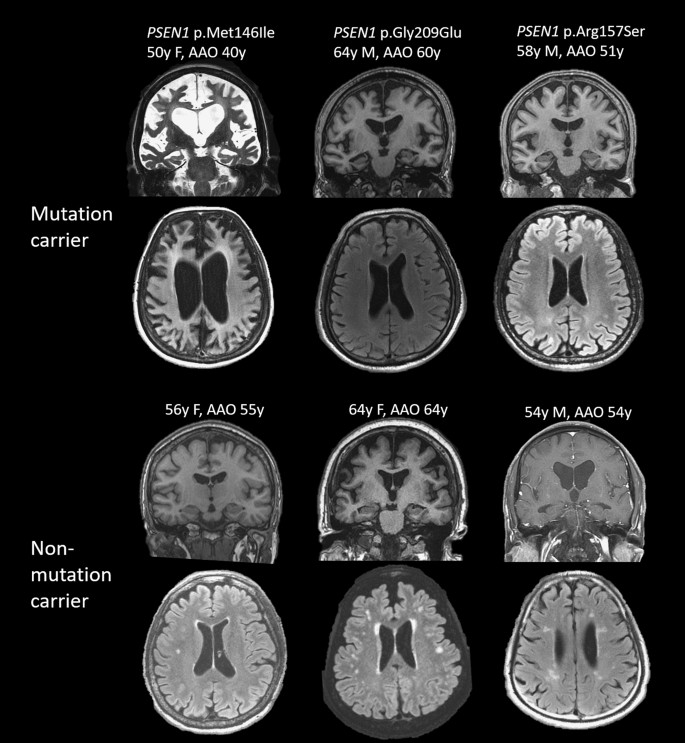

Brain MRI was available in 32 patients, including 11 with pathogenic mutations and 21 with no mutations found. The severity of MTA and PA did not differ between AD patients with and without mutations (p = 0.981 and p = 0.865, respectively). With adjustment of age, WMHs were significantly increased in those without mutations compared with those with mutations (B = 1.124, 95% CI 0.526–1.721, p < 0.001, VIF = 2.155) (Fig. 1).

Representative MRI of each of 3 age-matched mutation carriers and non-carriers. Coded in the order of scale of medial temporal atrophy, posterior atrophy (PA) and white matter hyperintensity (WMH), from left to right in mutation carriers are (4,3,0), (2,1,0) and (1,2,0) and non-carriers are (1,1,1), (1,1,2) and (3,0,2). Various degree of MTA was noted across patients with or without mutation; in the contrary, WMH was seen predominantly in non-mutation carriers.